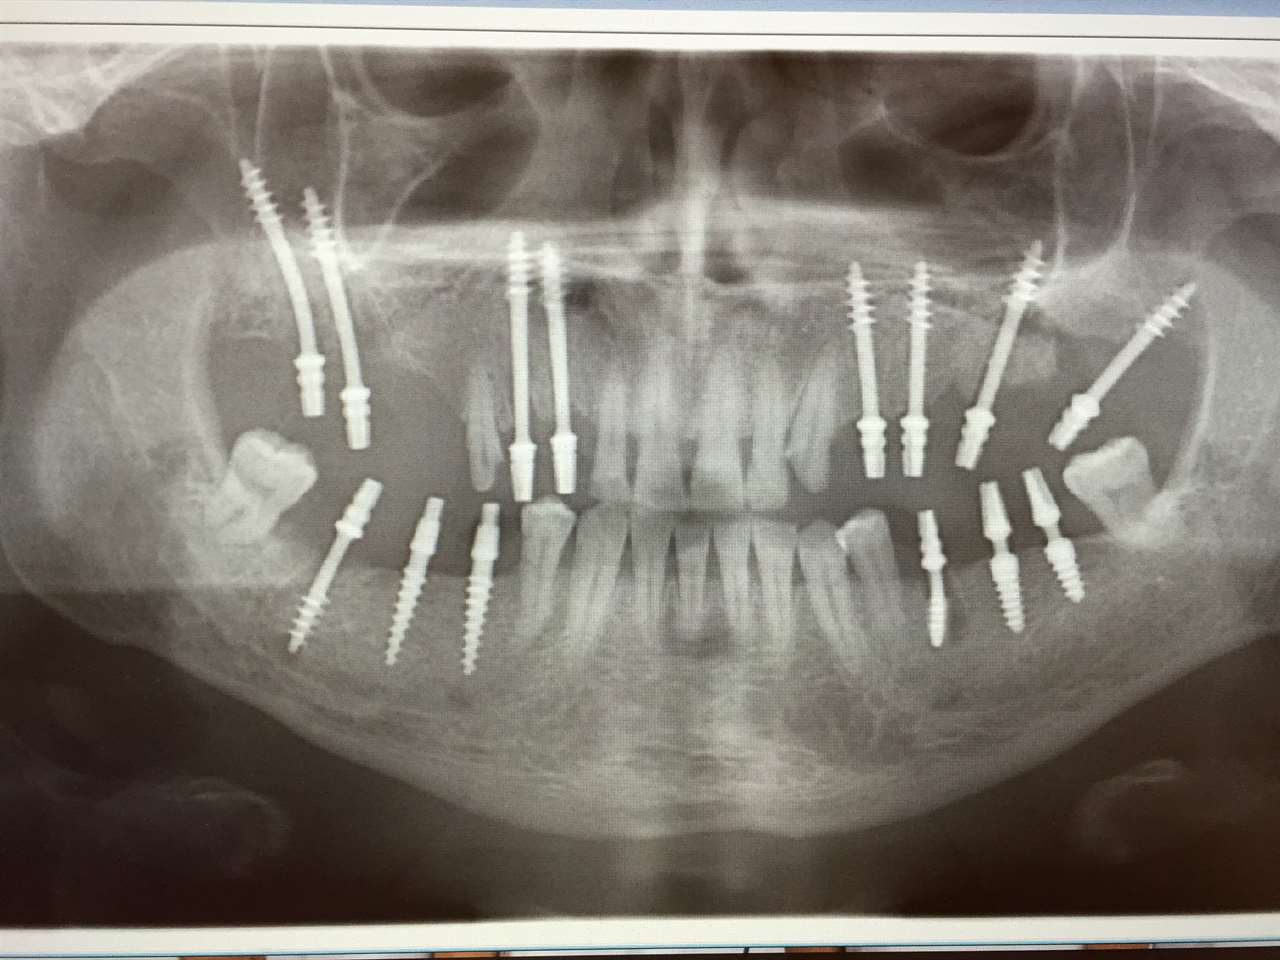

Teljes alsó,felső állcsont helyreállítása azonnal

terhelhető implantátumokkal és porcelán hidakkal.